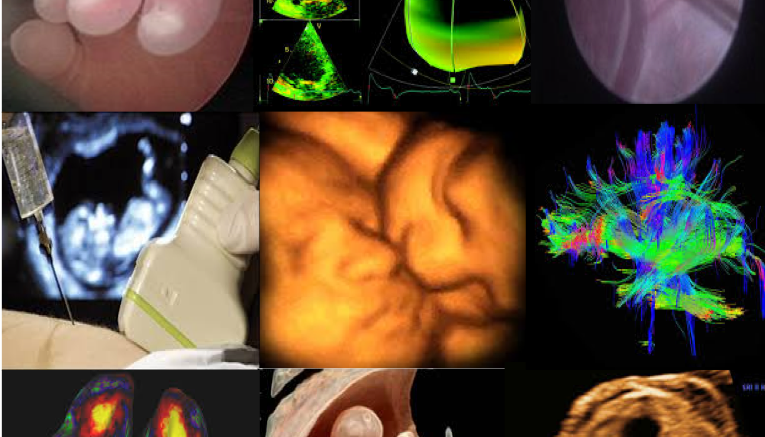

L’Università degli Studi “Gabriele d’Annunzio” di Chieti-Pescara è centro promotore del più grande studio internazionale sull’induzione del travaglio di parto nelle gravidanze affette da iposviluppo fetale tardivo. L’iposviluppo fetale è una condizione caratterizzata dall’impossibilità da parte del feto di raggiungere il proprio potenziale di crescita a causa dell’insufficienza della placenta. Tale condizione risulta esserne associata ad un più alto rischio di morte in utero e ad anomala performance cardiovascolare e neurocognitiva in età pediatrica, da cui l’importanza di una corretta gestione di queste gravidanze al fine di ridurne i rischi ad esso connessi. Al fine di condurre questo studio, i Professori Francesco D’Antonio, docente di Ginecologia e Ostetricia, Marco Liberati, Direttore della Clinica Ostetrico-Ginecologica della “’Annunzio”, hanno creato un gruppo di ricerca, il College (The induCtion of labOr in Late fetaL Growth rEstriction) Study Group, coinvolgendo i più importanti centri di medicina materno-fetale in Italia e Spagna.

“I risultati di questo studio – spiega il professor Marco Liberati, Direttore della Clinica Ostetrico-Ginecologica – suggeriscono che i feti affetti da iposviluppo tardivo sono a più alto rischio di scompenso ante-partum e che l’induzione del travaglio con metodiche non farmacologiche si associa ad un più basso tasso di complicanze per la madre ed il bambino e che quindi sono da preferire allorquando si decide di sottoporre ad induzione del parto tali donne”.

“La Clinica-Ostetrico-Ginecologica di Chieti e il suo centro di Gravidanze a Rischio e Medicina Prenatale che hanno coordinato questo studio – sottolinea il professor Francesco D’Antonio – sono già autori di numerose pubblicazioni sull’emodinamica cardiaca e cerebrale fetale nelle gravidanze complicate da queste patologie ed attualmente risultano promotori di più di 40 progetti di ricerca sulla medicina prenatale e gravidanze a rischio che coinvolgono i più importanti centri di medicina prenatale al mondo”.